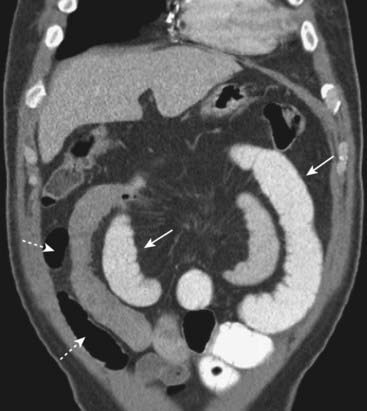

Figure 14-11 Closed-loop obstruction, CT.

A loop of small bowel (CL) is obstructed twice at the same point of twist (solid white arrow) producing a closed loop. No oral contrast enters the closed loop but is present in a more proximal loop of small bowel (dotted white arrow). Closed-loop obstructions are important because of their higher incidence of necrosis from strangulation of the bowel.